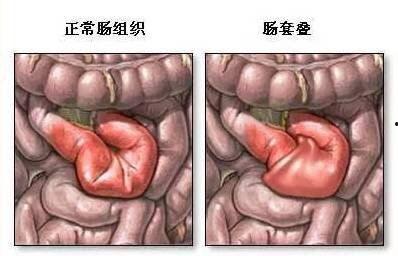

一、什么是肠套叠?

肠套叠,顾名思义,就是一段肠管套入另一段肠管中,导致肠内容物无法正常通过。这种状况在婴幼儿中较为常见,但你知道吗?成人也是有可能患上肠套叠的哦!